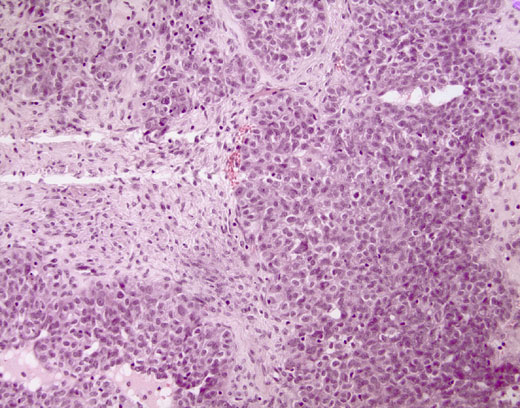

Cross-section #38 - 20X

click on the slide photo to see 40X magnification